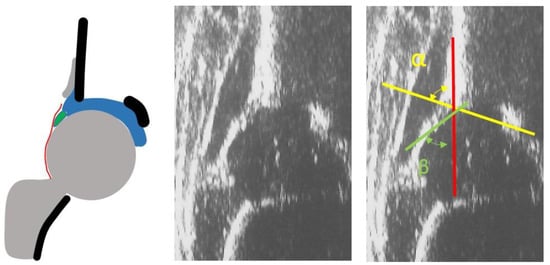

- infants with type I hips at the US examination according to Graf classification (Figure 1)

- infants with non-Type I hips at US examination according to Graf classification